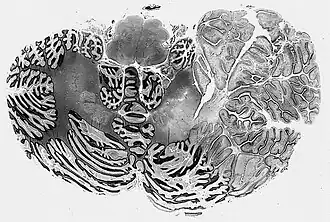

Description de cette image, également commentée ci-après

Histologie de la maladie de Lhermitte-Duclos

La microscopie de la maladie de Lhermitte-Duclos montre les caractéristiques suivantes :

1. Feuilles cérébelleuses circonscrites élargies

2. La couche granuleuse interne est focalement indistincte et occupée par de grandes cellules ganglionnaires

3. Pistes myélinisées dans la couche moléculaire externe

4. La substance blanche sous-jacente est atrophique et gliotique